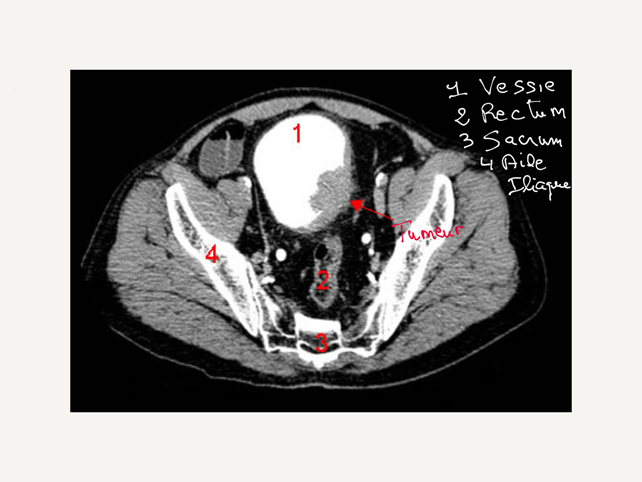

L’uroscanner

L’uroscanner est une imagerie en coupes qui est basée sur l’utilisation des rayons X. Au cours de l’examen, il est réalisé une injection intraveineuse de produit de contraste qui permet de visualiser les structures de l’appareil urinaire, les reins, les uretères, la vessie notamment.

L’uroscanner renseigne sur la taille, l’aspect, la localisation de la tumeur de vessie au niveau de l’appareil urinaire et de ses différentes portions, et notamment au niveau de la vessie.

Elle permet également l’étude des aires ganglionnaires notamment au niveau iliaque. Les ganglions peuvent être envahis par le cancer ainsi que d’autres organes intra-abdominaux ou pelviens.

La réalisation de l’uroscanner a supplanté actuellement l’urographie intraveineuse qui était réalisée autrefois car les renseignements qu’il apporte sont supérieurs.